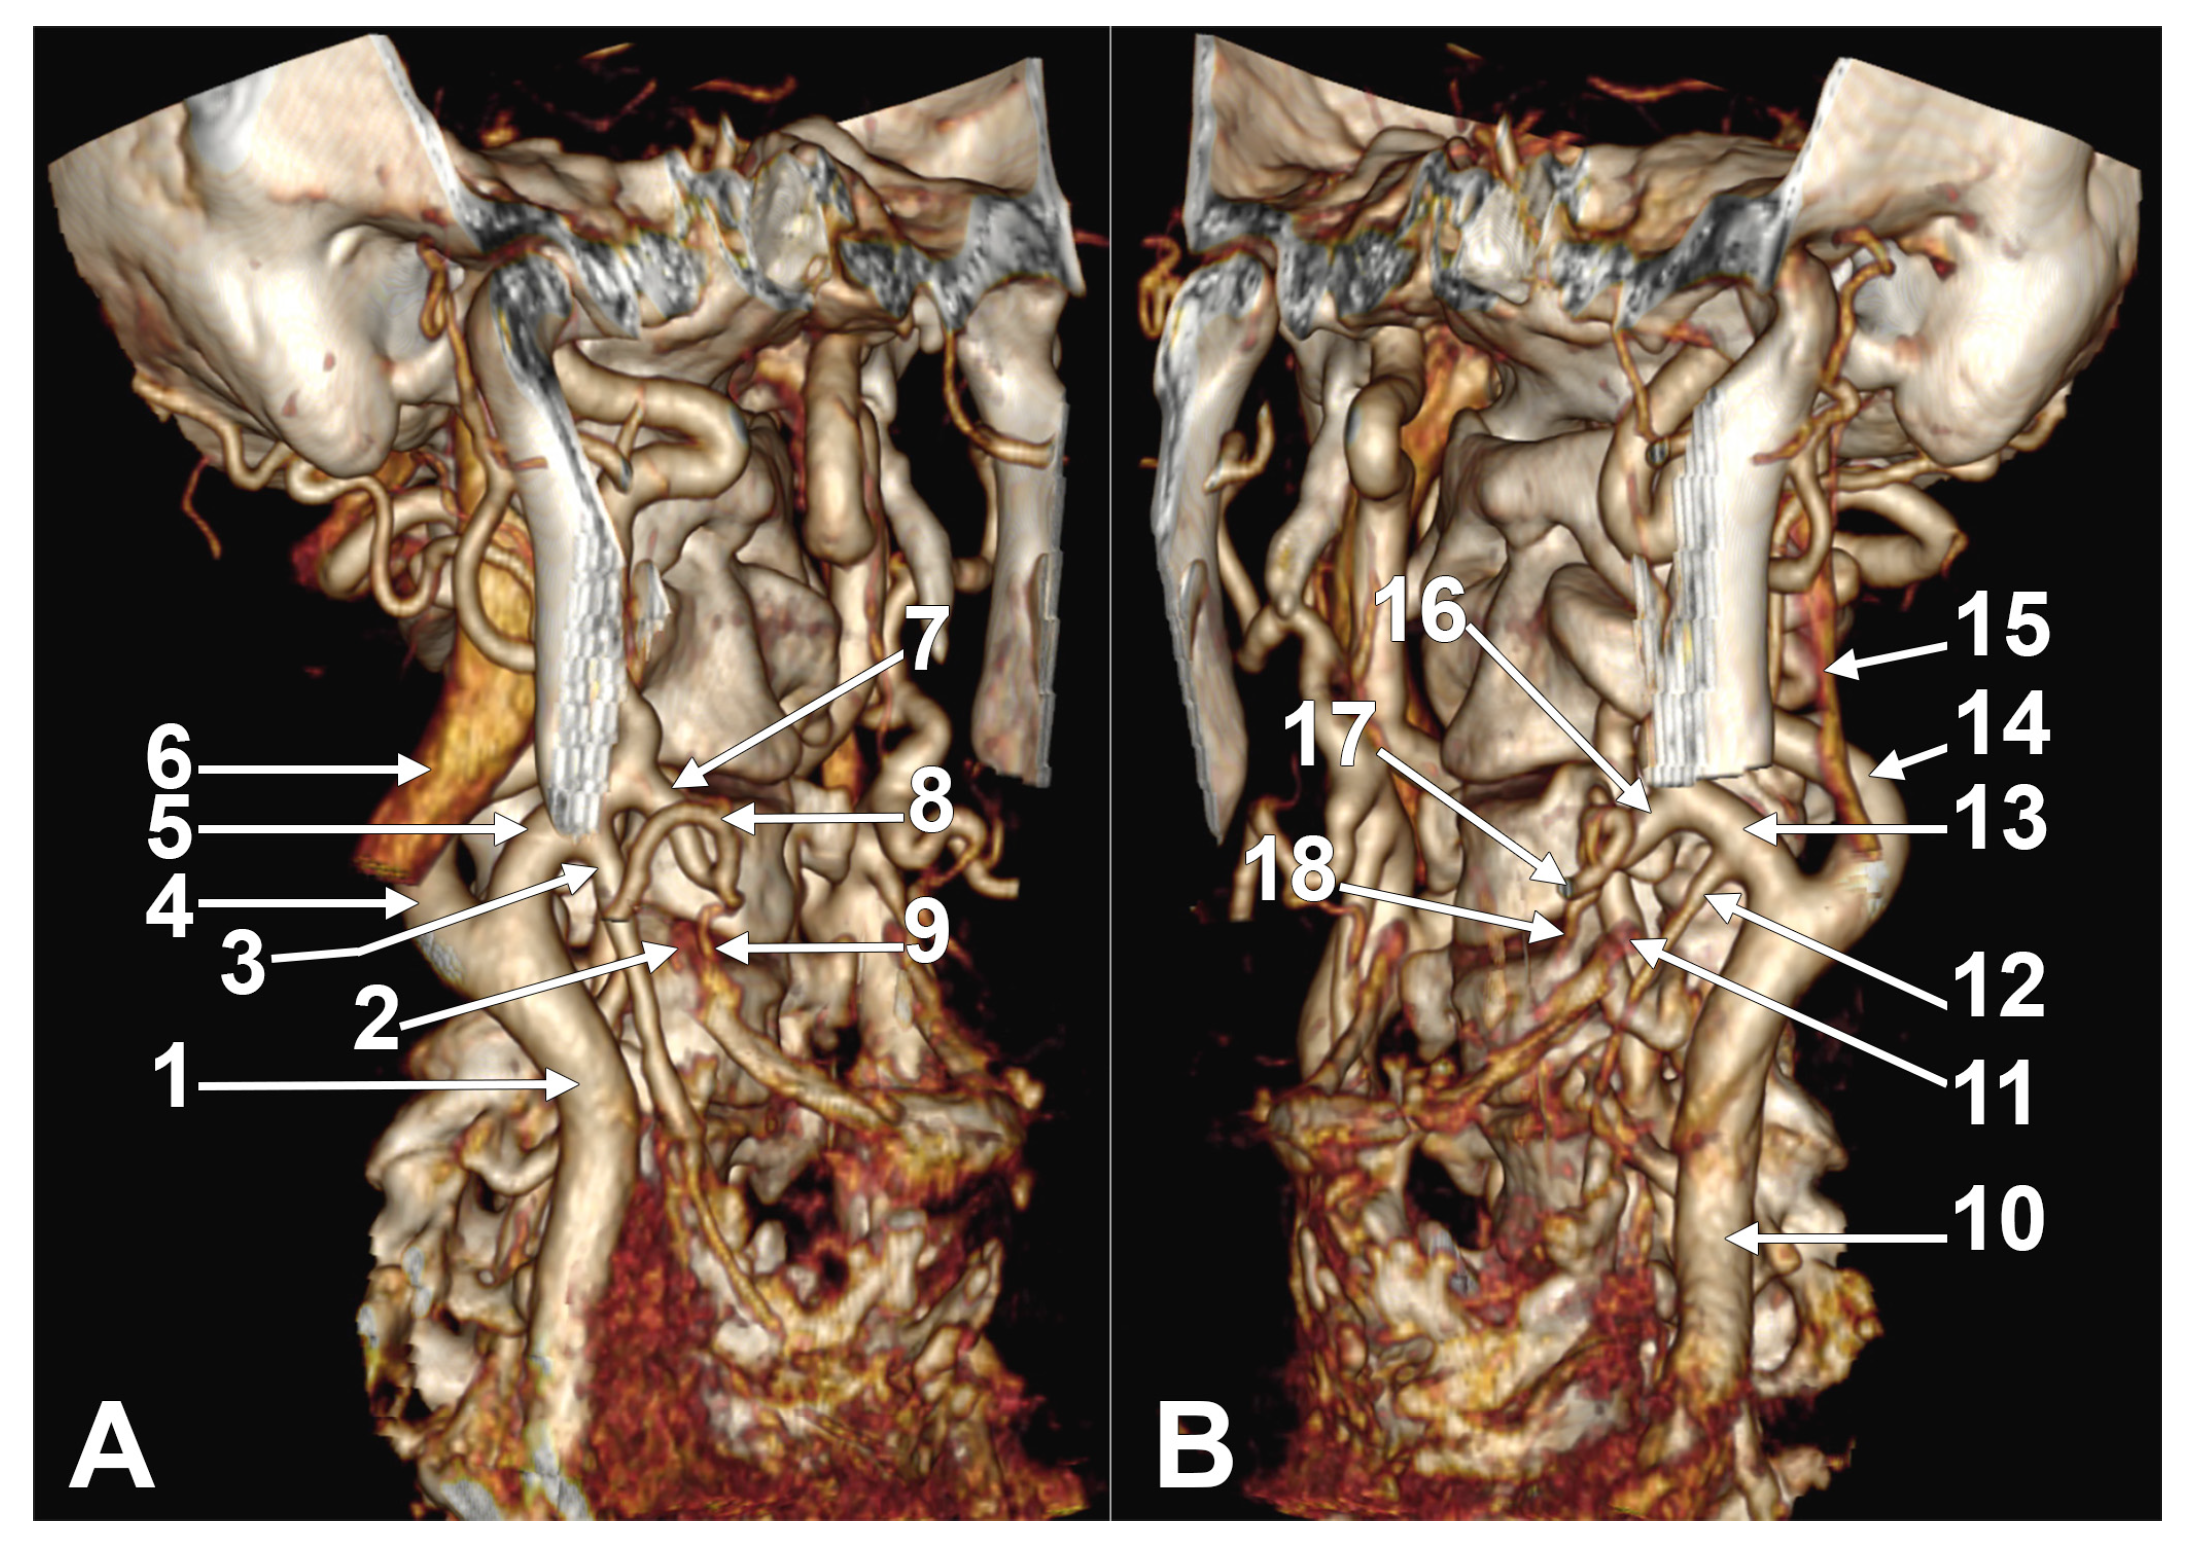

Appendix A.2. Supplemental Figures

- Calota, R.N.; Rusu, M.C.; Dumitru, C.C.; Moraru, L.; Tudose, R.C. Retropharyngeal course of the superior thyroid artery—A novel finding. Surg. Radiol. Anat. 2025, 47, 115. [Google Scholar] [CrossRef] [PubMed]